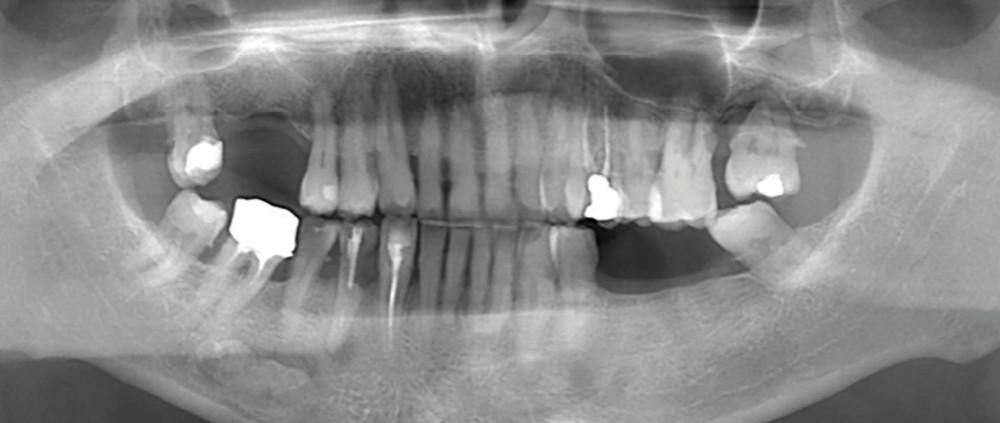

Réalisation d’une radiographie panoramique chez un patient âgé de 62 ans, sans/avec symptomatologie douloureuse.

Quelle anomalie radiologique observez-vous sur cette radiographie panoramique ?

Comment…